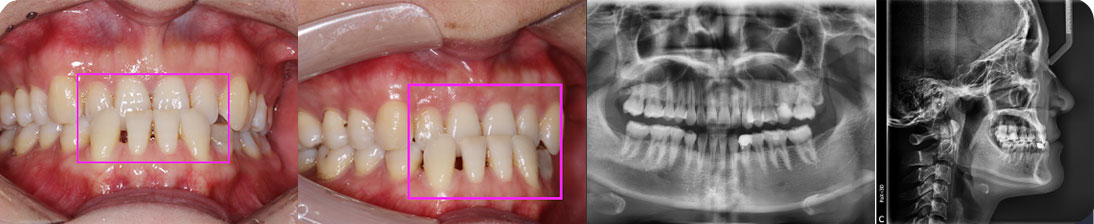

• 【診斷】

骨性I類,均角,安氏I類

上牙列重度擁擠,下牙列輕-中度擁擠

上中線右偏

13唇側錯位

• 【治療方案】

拔除14,排齊上牙列

下頜尖牙適當擴弓,配合適量鄰面去釉,排齊下牙列

上頜左側配合適量鄰面去釉,調整中線

盡量調整后牙為尖窩咬合關系